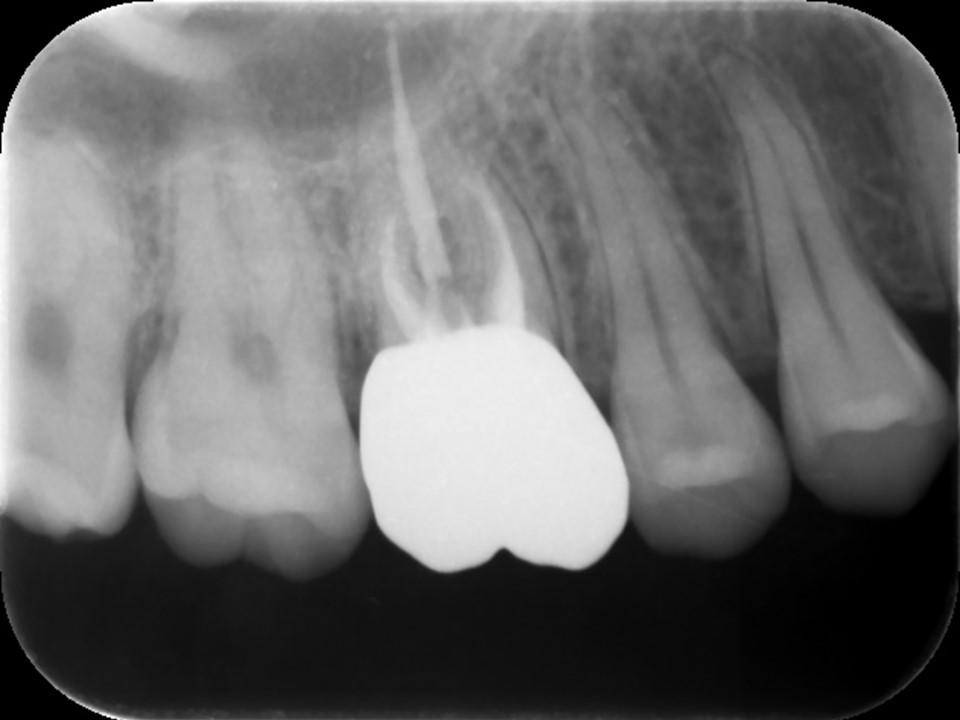

根管充填後のレントゲン画像です。パーフォレーション部にバイオセラミックセメントが充填されているのが分かります(赤矢印)。

根管治療7か月後のレントゲン画像です。根尖病変はきれいに治癒し、骨の再生を認めます(黄矢印)。パーフォレーション部も骨吸収は認めず、予後は非常に良好です。